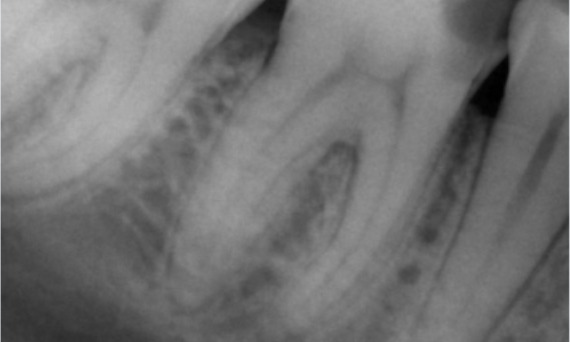

Un caso complejo con raíces largas y un sistema calcificado con un seguimiento de 14 meses

"Un éxito centrado en el paciente y el proceso". - Dr. Cowie

Antes: Radiolucencia periapical asociada principalmente con la raíz distal y pérdida de la lámina dura en la raíz mesial.

Después: En este caso, se eligió TruNatomy para permitir un enfoque apalancado en las caries y un enfoque en la conservación de la dentina pericervical, especialmente en el aspecto mesial donde el diente tuvo una restauración más mínima.